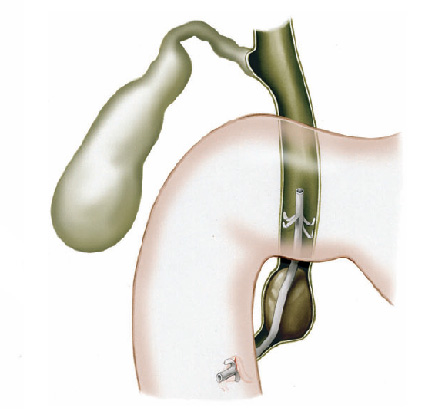

Pacientes que têm o objetivo de emagrecer, podem ter como alternativa a passagem de um balão intragástrico. A passagem do balão é realizada por endoscopia e o procedimento dura cerca de 20 a 30 minutos.

Passagem de Balão Intragástrico

1. O balão intragástrico é introduzido desinsuflado durante a endoscopia e colocado no estômago.

2. Um líquido azul (azul de metileno diluído em soro fisiológico) é colocado dentro do balão através de uma válvula. O volume varia entre 500-700 ml.

3. O aparelho de endoscopia é removido e o balão intragástrico pode ser deixado por um período de até 6 meses.

Como funciona o balão intragástrico?

O balão intragástrico ocupa um espaço dentro do estômago e o paciente fica com sensação de plenitude e saciedade precoce. Em outras palavras, sobra menos espaço para os alimentos, diminuindo o volume ingerido nas refeições.

Pacientes que têm o objetivo de emagrecer, podem ter como alternativa a passagem de um balão intragástrico. A passagem do balão é realizada por endoscopia e o procedimento dura cerca de 20 a 30 minutos.

Passagem de Balão Intragástrico

1. O balão intragástrico é introduzido desinsuflado durante a endoscopia e colocado no estômago.

2. Um líquido azul (azul de metileno diluído em soro fisiológico) é colocado dentro do balão através de uma válvula. O volume varia entre 500-700 ml.

3. O aparelho de endoscopia é removido e o balão intragástrico pode ser deixado por um período de até 6 meses.

Como funciona o balão intragástrico?

O balão intragástrico ocupa um espaço dentro do estômago e o paciente fica com sensação de plenitude e saciedade precoce. Em outras palavras, sobra menos espaço para os alimentos, diminuindo o volume ingerido nas refeições.